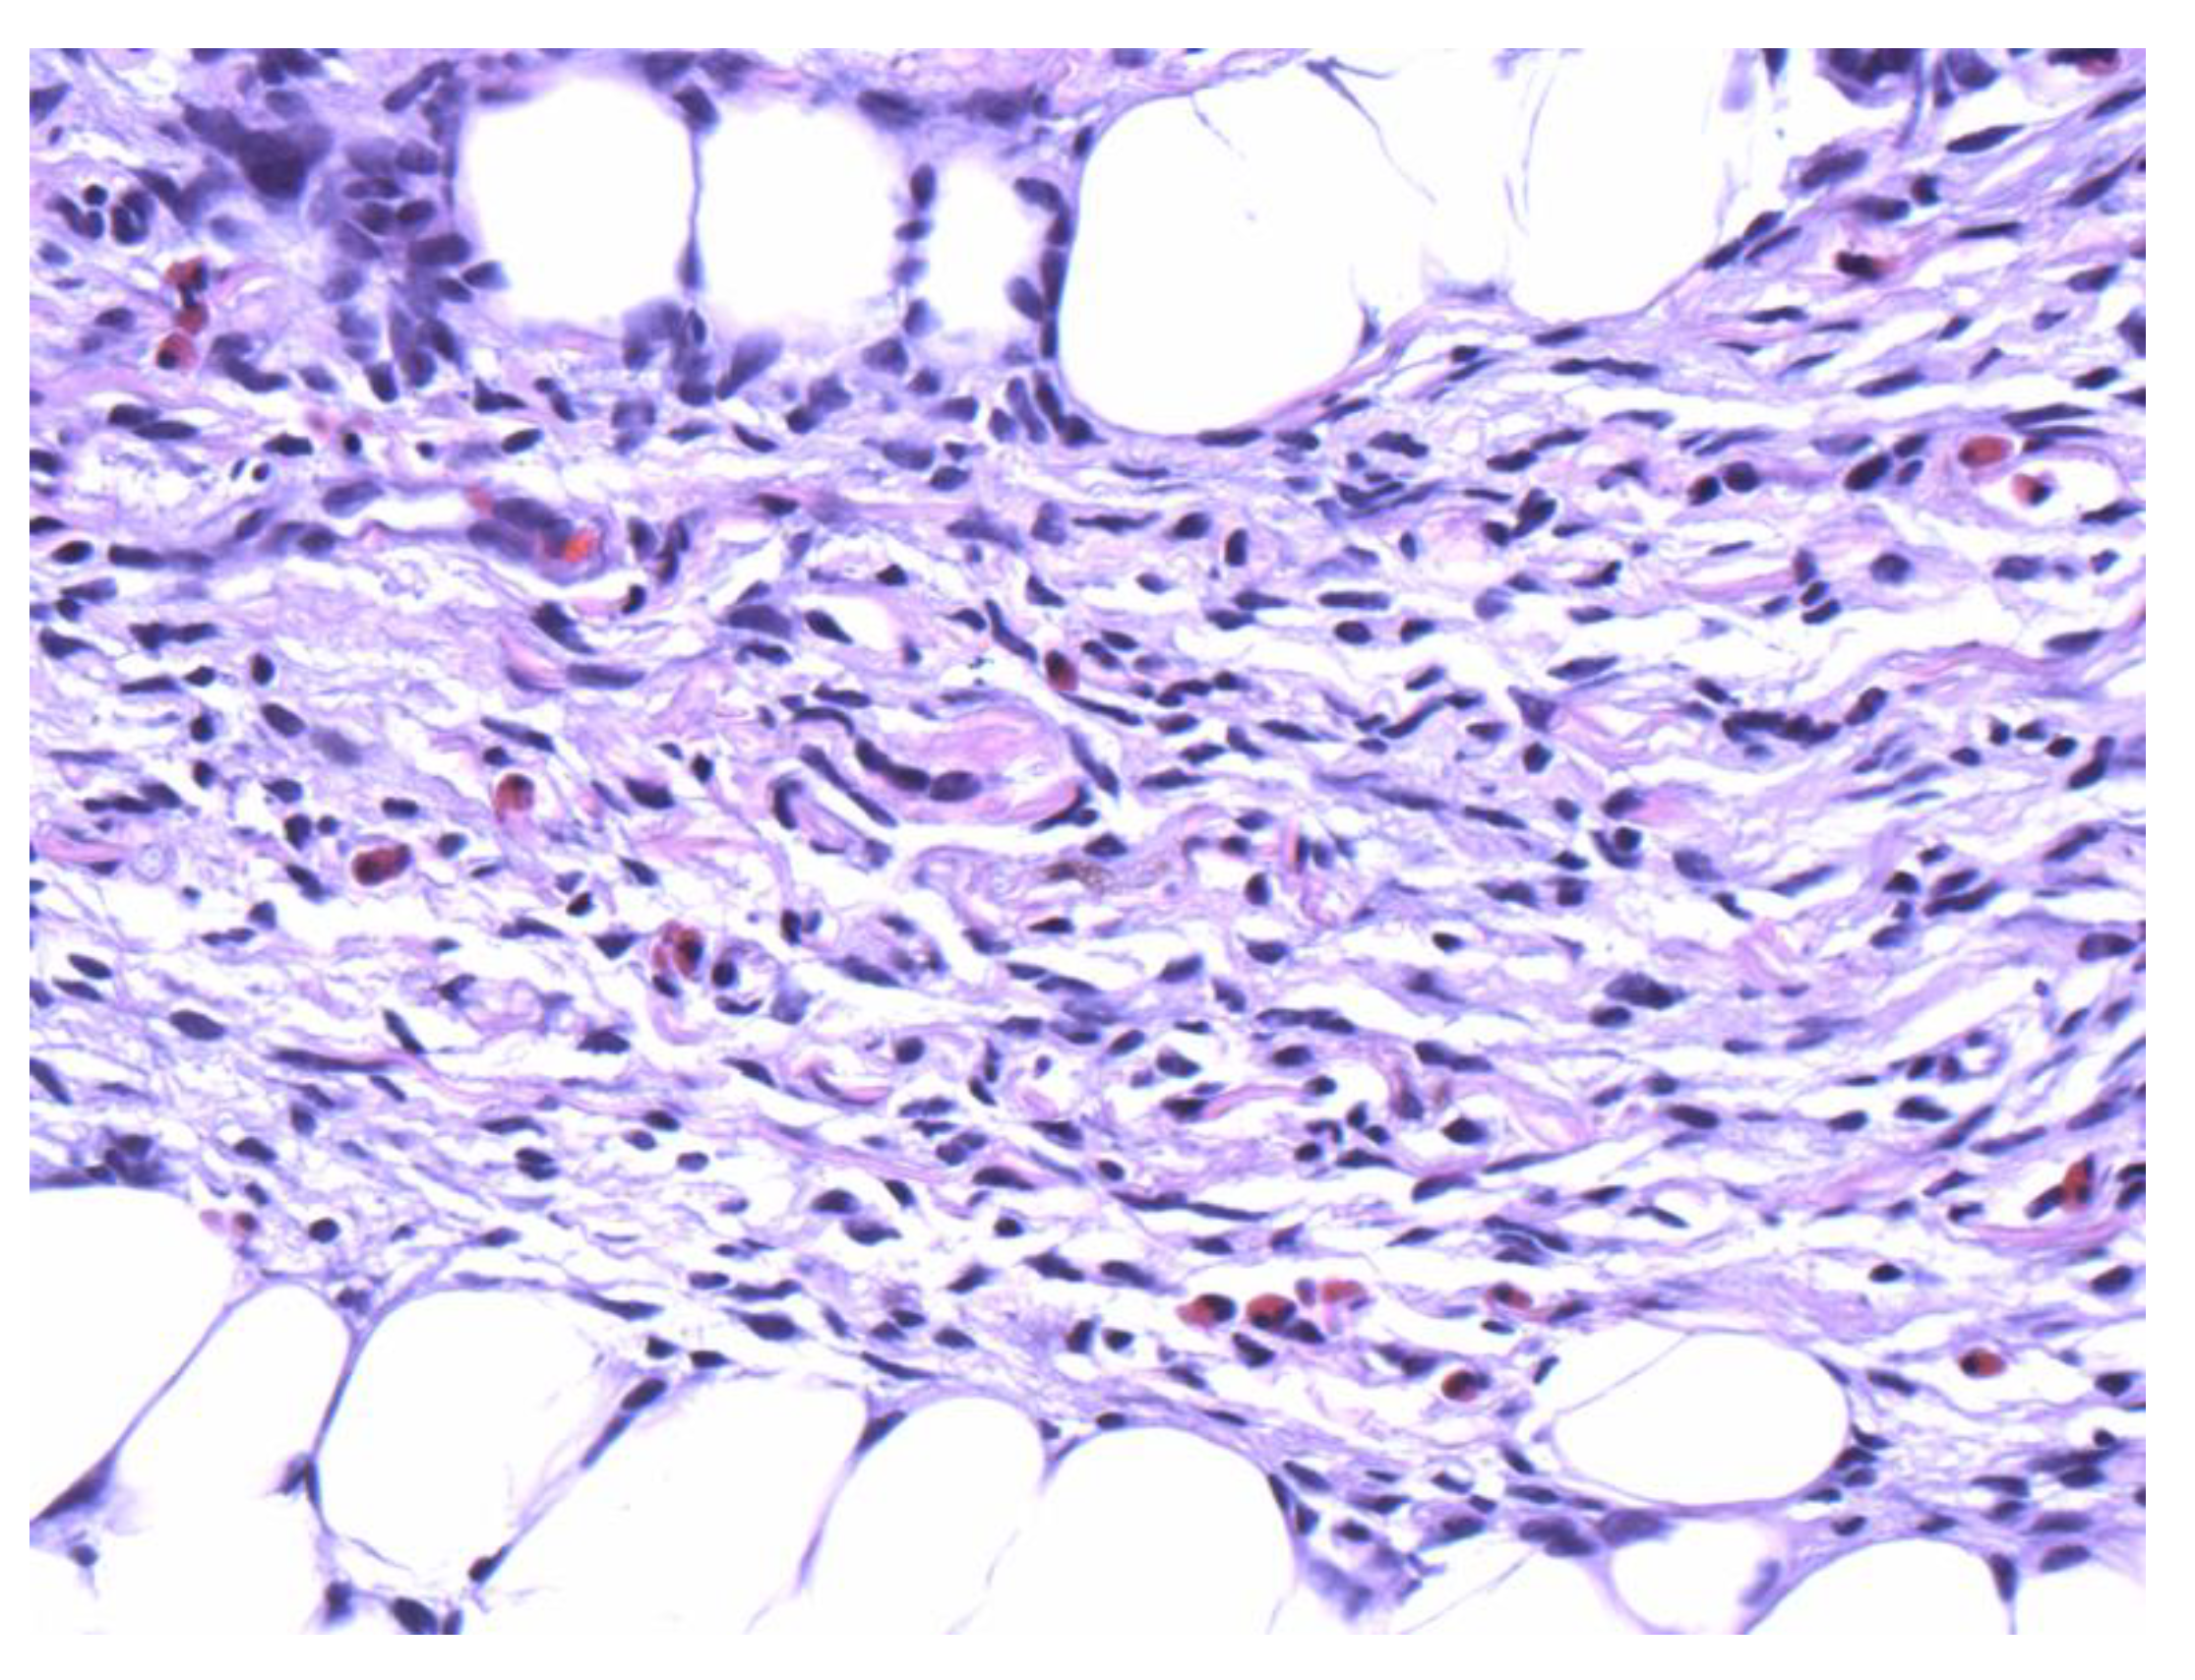

Figure 3.

Numerous eosinophils are scattered within the spindle cell proliferation (40×).